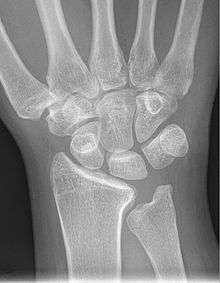

Shown is the right hand, palm down (left) and palm up (right). Proximal: A=Scaphoid, B=Lunate, C=Triquetral, D=Pisiform Distal: E=Trapezium, F=Trapezoid, G=Capitate, H=Hamate | |